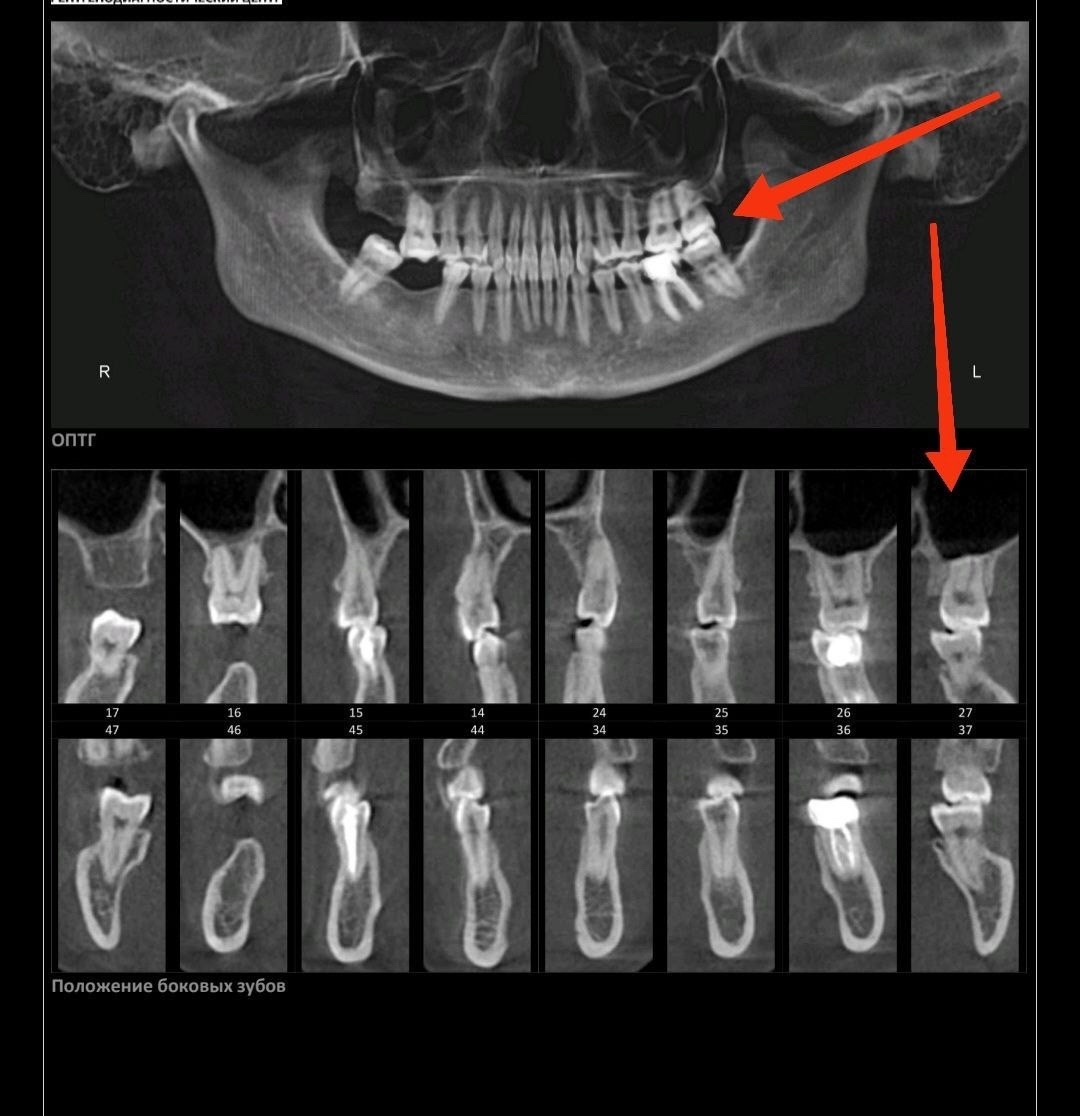

В чате курса девушка прислала снимки КТ стоя и МРТ лежа. Специалист сразу задала вопрос, что произошло, оказалось, просто положение тела разное.

К вопросу о том, почему нельзя регистрировать прикус лежа в кресле стоматолога, изготавливая в итоге под лежачее положение пломбы, коронки и прочие приблуды.

Это как и с зубами: лечить или сделать слепки удобнее, конечно, лежа - положение не имеет значения. Но именно для понимания истинной картины того, как челюсти и зубы стоят относительно друг-друга, требуется вертикальное положение.